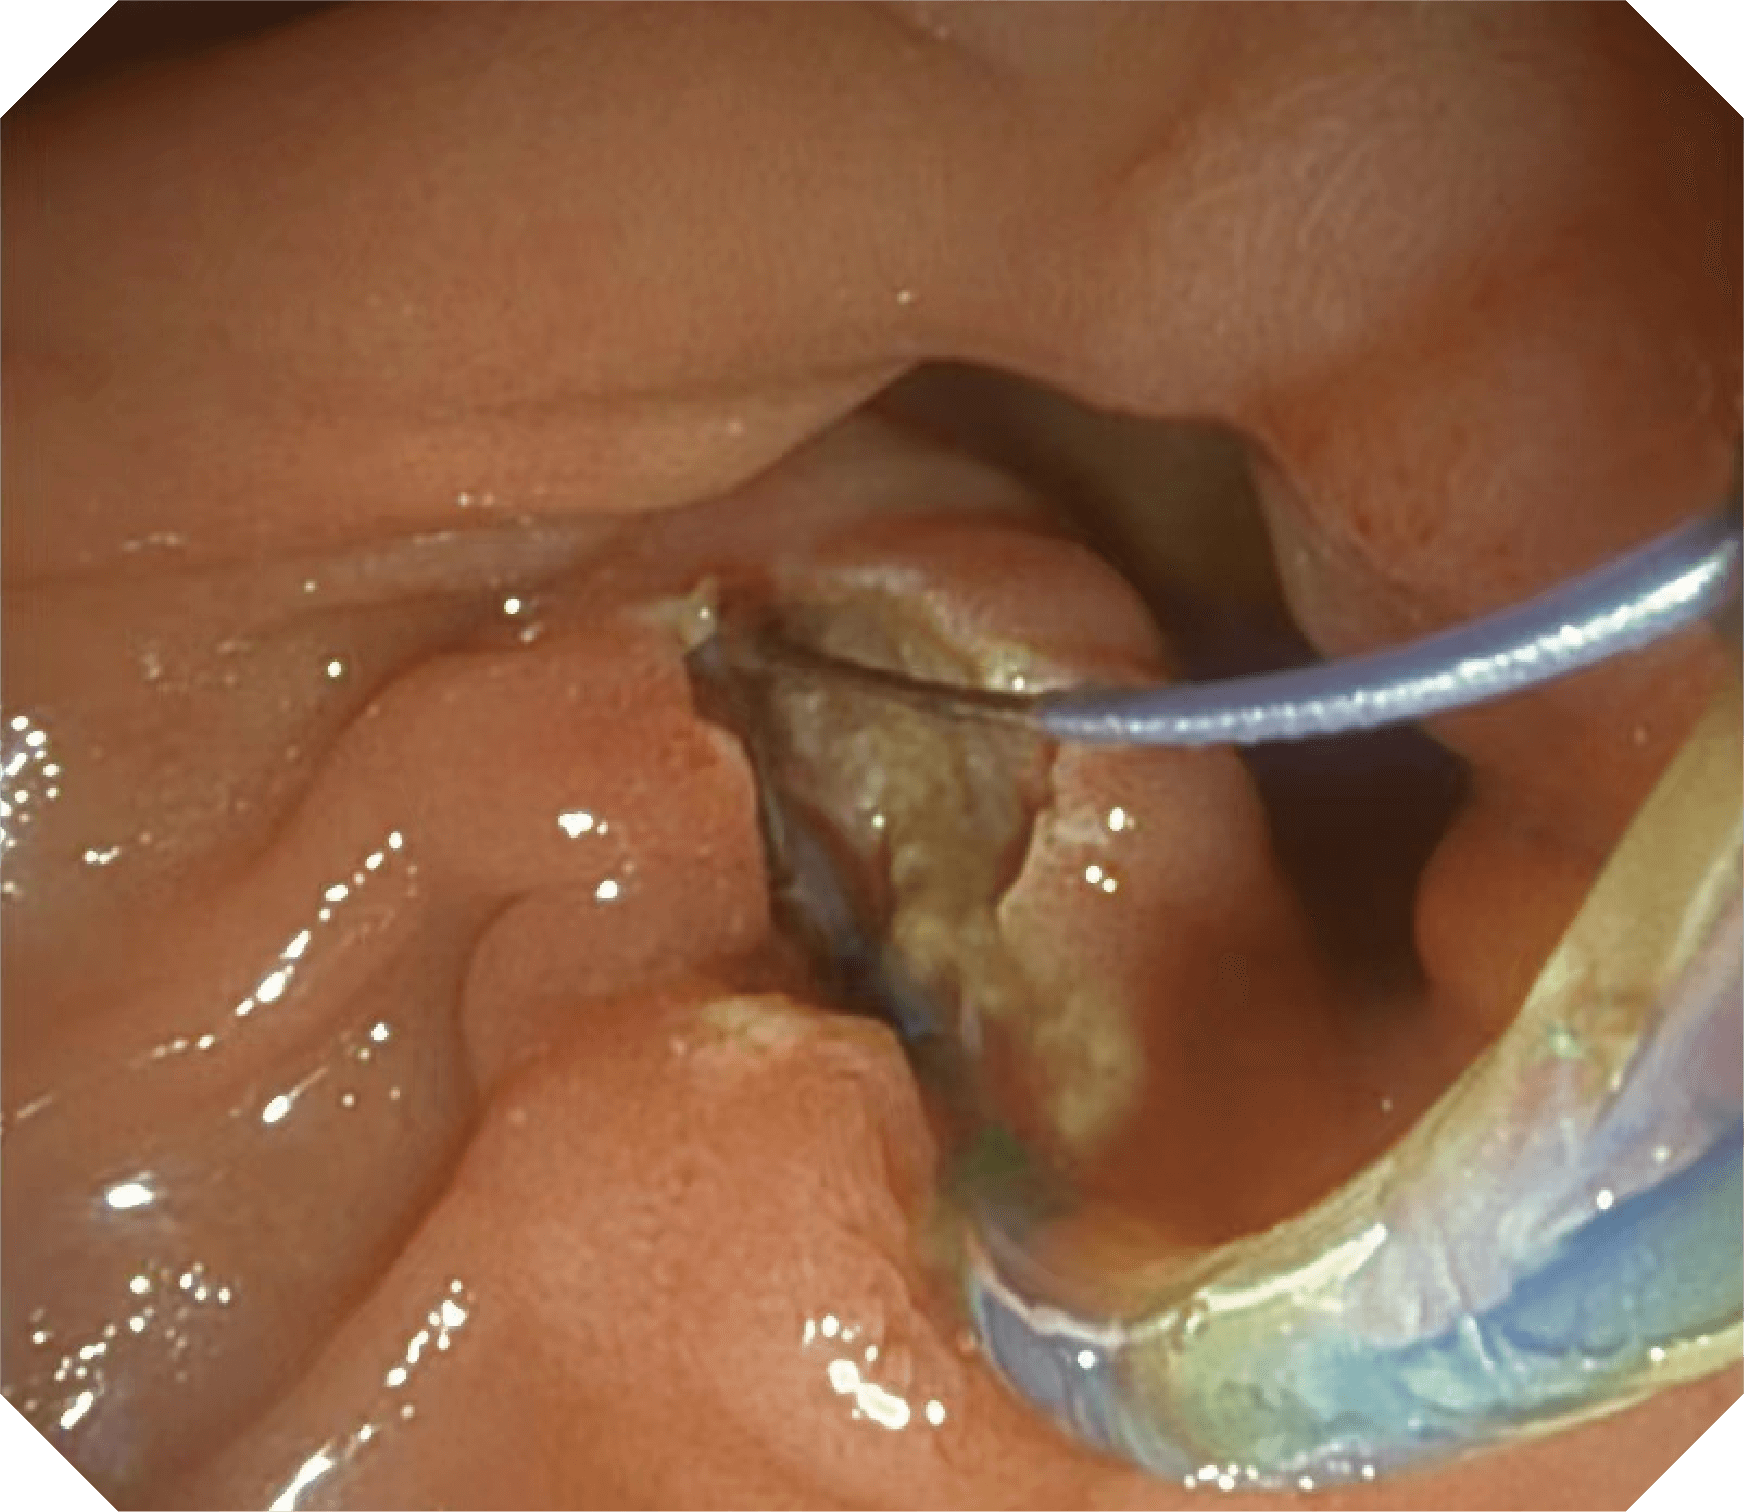

CMOS传感器提供高清内镜视野 SFI/VIST光学染色技术凸显病变区域

4.2mm大钳道,器械交换更顺畅

导丝机械锁紧功能

V槽设计提升导丝控制

优异的手术器械抬举性

当切开刀伸出视野外时,导向面引导其回归视野